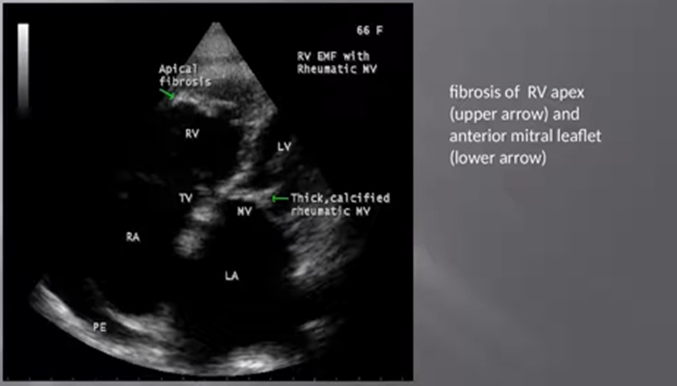

RF (Rheumatic fever and EMF may coexist in the same patient as shown in Figures 46 & 47.

Figure 46: showing fibrosis of RV apex (upper arrow- EMF) and anterior mitral leaflet (lower arrow- RF)